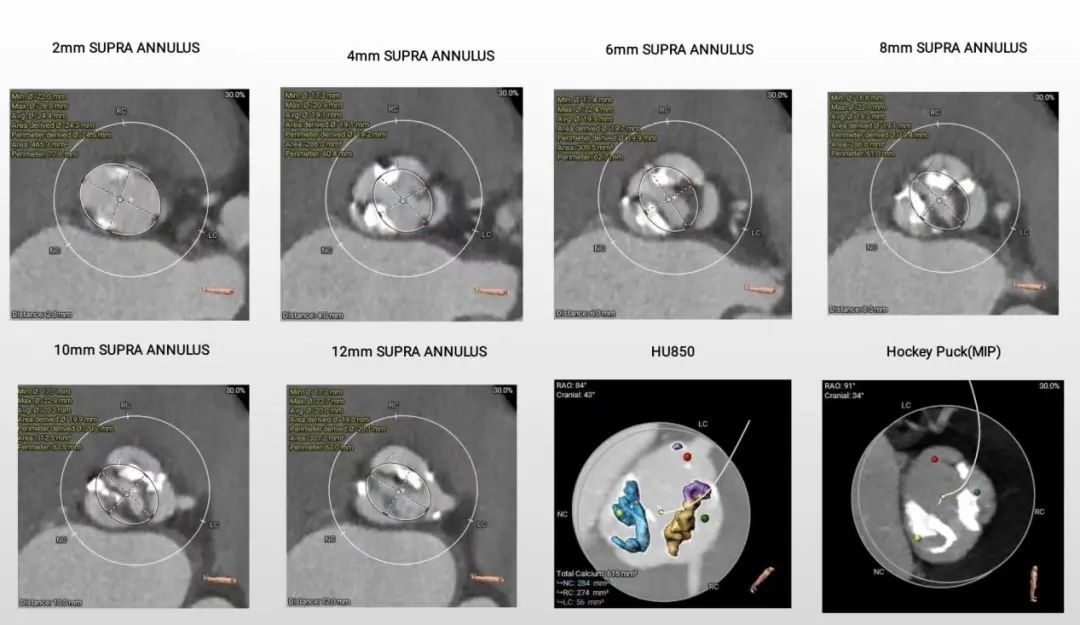

1.主动脉瓣瓣环周长80,平均周长径25.5;

2.Type1型二叶式主动脉瓣,R-L纤维融合嵴,瓣叶增厚,重度钙化,钙化分布不均匀,钙化呈团块样分布在无窦窦底及左冠瓣叶处,左室流出道开口呈敞口状;

3.左冠及STJ开口较低,瓣叶冗长,左、右冠瓣叶长度>冠脉顶端开口到瓣叶附着距离;

4.瓦式窦内径、窦管交界内径偏小,升主动脉内径尚可;

5.主动脉瓣环与水平夹角为50°,非横位心,主动脉弓距及弓部夹角尚可,主动脉弓存在散在钙化;

主动脉根部评估:

瓣环上解剖结构评估: